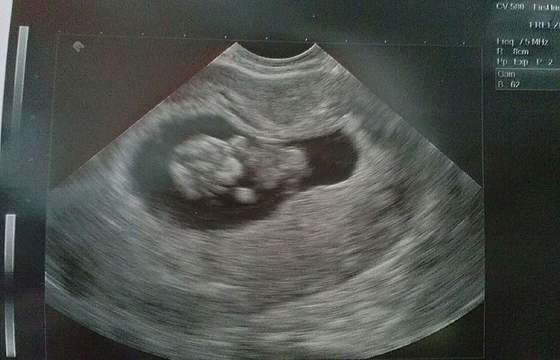

ja tak wyglądałam w 19 tyg

i w 20..

z tego co patrzę to zaczął mocniej rosnąć po 23 tyg